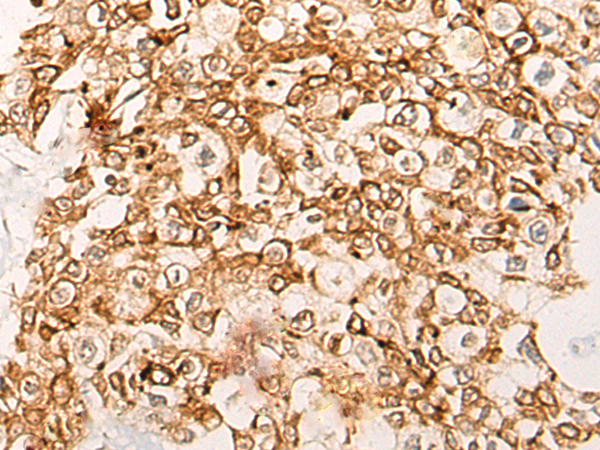

The image is immunohistochemistry of paraffin-embedded Human prostate cancer tissue using 46996(CWF19L1 Antibody) at dilution 1/20. (Original magnification: ?00)